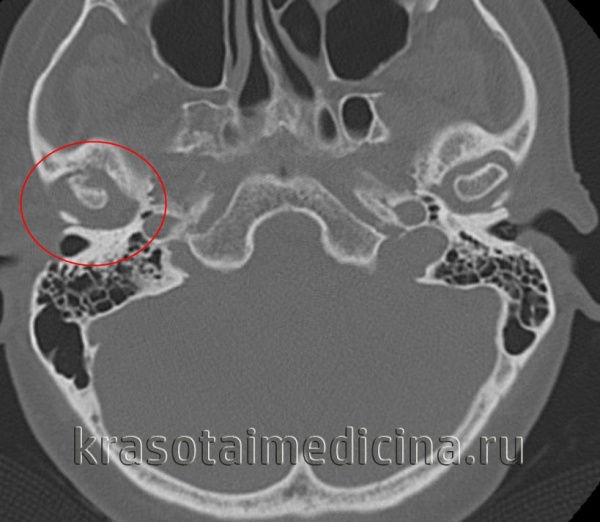

Проведены МРТ ВНЧС, по данным которой определяется полная вентральная дислокация обоих дисков ВНЧС без репозиции, и конусно-лучевая компьютерная томография (КЛКТ) лицевого скелета, обнаружившая наличие асимметричной скелетной деформации за счет уменьшения задней лицевой высоты и размеров обоих мыщелковых отростков. С целью определения дальнейшей тактики ведения пациентки и проведения комплексного лечения имеющихся хронического болевого синдрома и деформации лицевого скелета консультирована совместно челюстно-лицевым хирургом, ортодонтом и неврологом, а в последующем, после обнаружения высоких титров вируса герпеса человека 6-го типа (ВГЧ-6) в крови и слюне, направлена к дерматовенерологу в Герпетический центр. Диагностированы дисфункция ВНЧС, асимметричная деформация лицевого скелета с тенденцией к вертикальному типу роста, мигрень без ауры, постгерпетическая нейропатия II ветви правого тройничного нерва (ВГЧ-6).

КТ ВНЧС. Артроз правого височно-нижнечелюстного сустава: деформация мыщелка нижней челюсти, сужение суставной «щели», остеофиты.